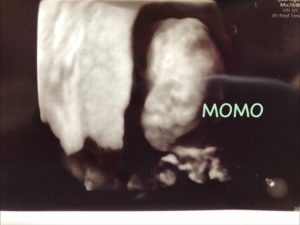

今回も少しだけ4Dエコーして貰って、なんとなくウェウェちゃんに似ていました。